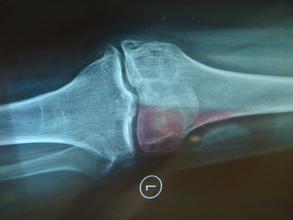

膝关节退行性关节炎又称膝关节肥大性关节炎,多见于老年人,因而也称作老年性关节炎。 》》》老年人膝关节退行性关节炎怎么办?点击咨询

膝关节退行性骨关节炎的表现

膝关节疼痛是膝关节退行性关节炎的主要症状,表现为钝痛,晨起或关节处于某一位置过久后,疼痛较为明显,稍加活动即可减轻。但活动过多时,由于膝关节摩擦又感疼痛,气候变化时疼痛加重。患者感到膝关节不灵活,休息后更觉明显。膝关节出现僵硬状态,活动时膝关节可发出粗糙的摩擦声。这些症状可随着病理变化的加剧而加重。除疼痛外,局部地区肿胀、有渗液,肌肉萎缩,甚至出现关节畸形,活动受限。》》》有症状出现怎么办?点击咨询